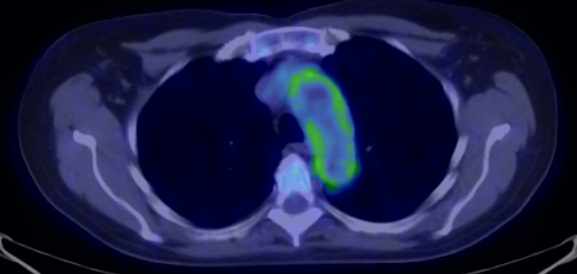

The greatest precision of image registration is achievable if the patient experiences minimal motion differences (the patient lies in the same position and imaging takes place almost at the same time) during both examinations. These requirements are met in hybrid imaging methods, with the implementation of the so called hardware registration. PET-CT, SPECT-CT or the newly emerging PET-MR examinations are all able to utilize hardware registration. The integrated PET/SPECT-CT method represents the latest technical developments of both PET and CT scanners, combined in one machine. It is capable to represent structural and metabolic information simultaneously and identically. The machine’s PET/SPECT and CT components are aligned along the common axial axis, and as the patient table moves along their longitudinal axis, the two examinations are carried out only minutes apart from each other, minimizing any movement or change in the patient’s position. During evaluation the identical slices of CT and PET can be matched with each other and they can be analyzed independently or represented in a fusion image. (Figure 1.)

1. Fusion images; FDG PET-CT, transversal and coronal planes. The dominance of certain components (transparency) can be constantly adjusted on the fused image.